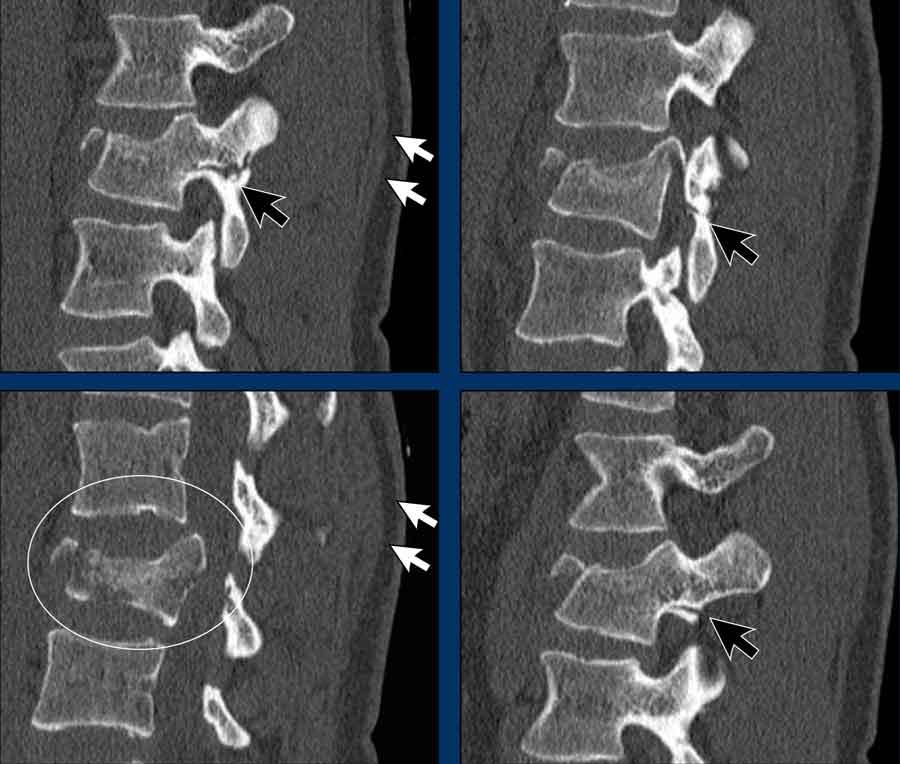

Findings

- The most severe level is L4/5 with dislocation (dotted lines)

- Facet fractures at L4 (arrows).

- A4 burst fracture (circle).

Conclusion:

Injury type C + A4 at L4/5.